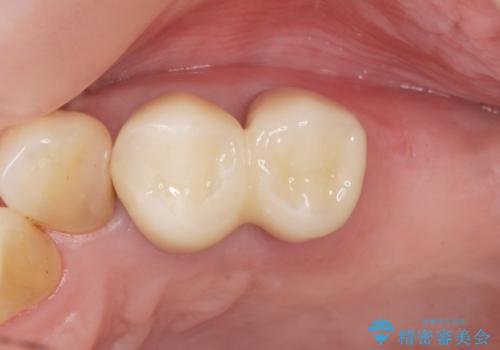

- ¥506,000 (再根管治療×2本、土台×2本、仮歯×2本、クラウン×2本) ※税込費用は治療当時の料金となります

気にされていた歯の動揺や違和感がなくなり、喜んで頂けました。

モチベーションがあがり、大臼歯欠損部位の治療に関しても前向きに検討して下さるとの事でした。

クラウンの種類:オールセラミッククラウン スタンダード